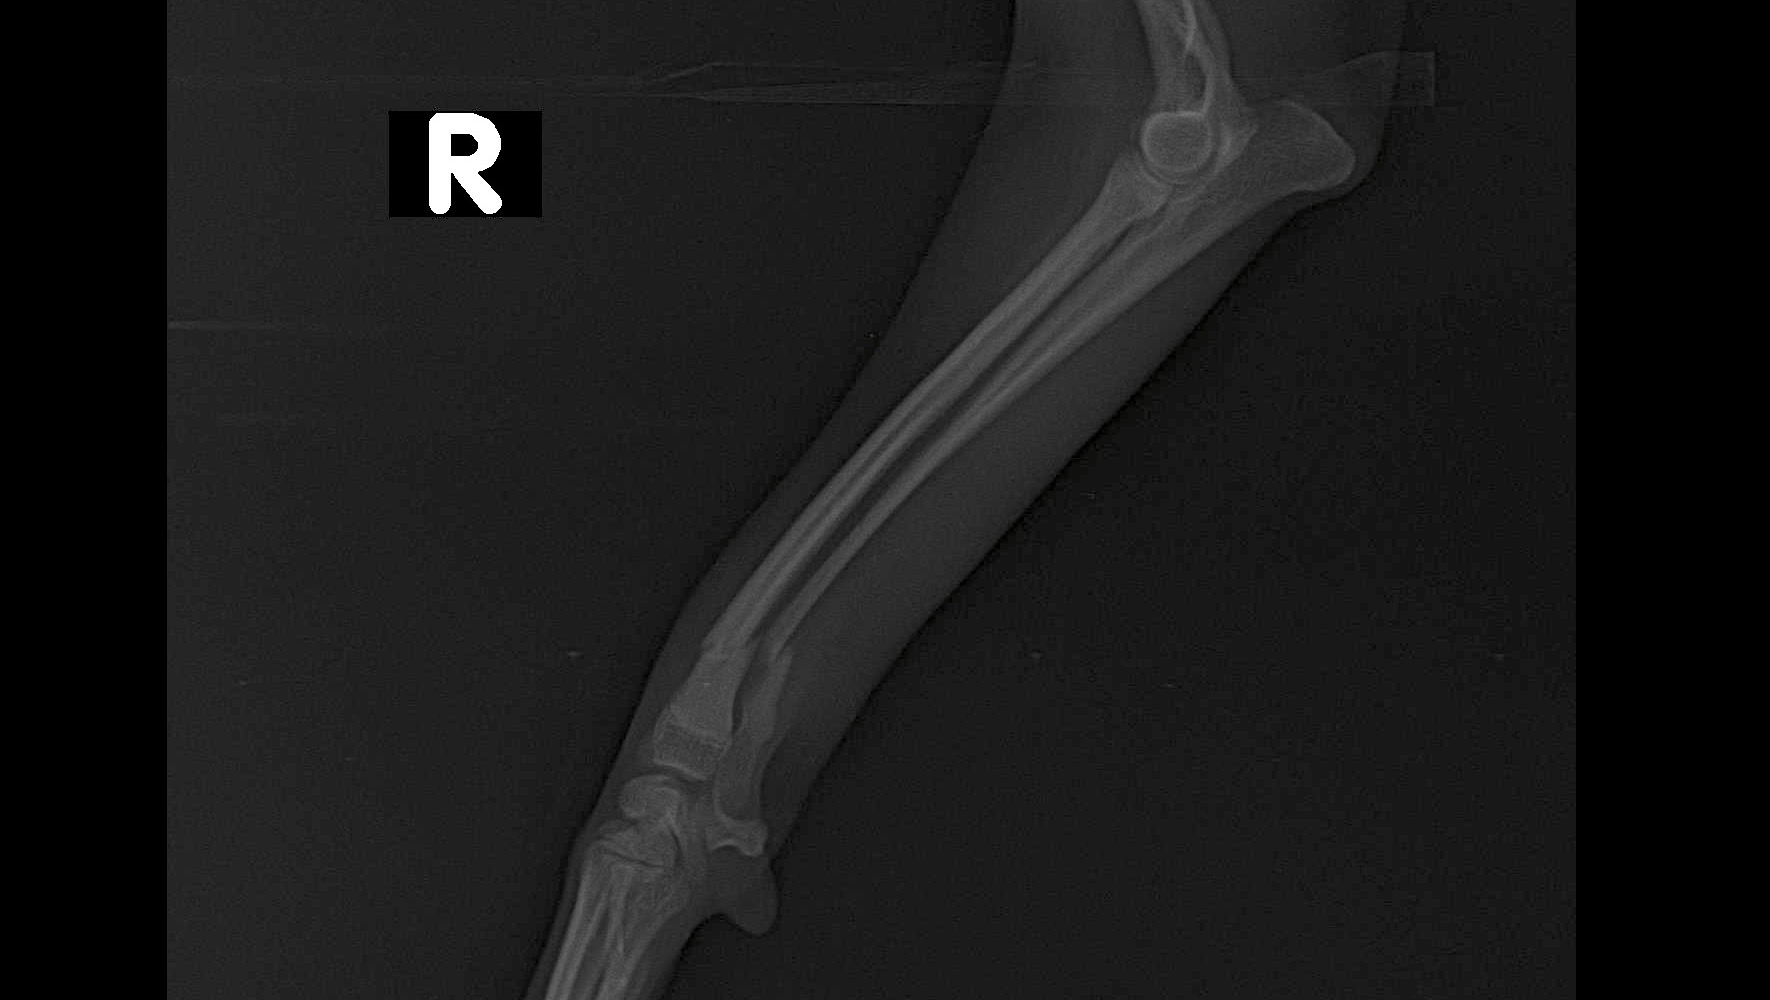

Hace unos días, mientras bajaba las escaleras con mi hermano, tropecé y caí. El golpe fue tan fuerte que me rompí dos huesos de mi patita. Ahora necesito una cirugía urgente en los próximos 6 días, pero el costo es alto y mi familia no puede cubrirlo todo.

Pero ahora estoy así: